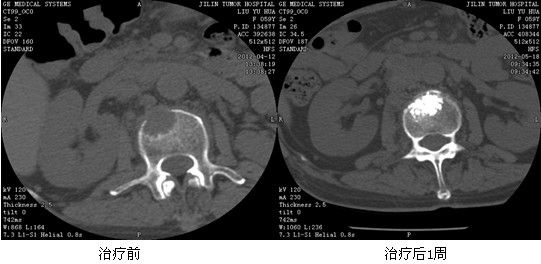

典型病例:趙XX,女,38歲,原發(fā)性肝右葉癌(BCLC C期)、多發(fā)性骨轉(zhuǎn)移癌。左側(cè)髖部及第4腰椎發(fā)現(xiàn)轉(zhuǎn)移,左髖部疼痛明顯,腰背部疼痛明顯。給予125I放射性粒子植入及骨水泥局部填塞治療后疼痛癥狀明顯減輕,病灶明顯萎縮。